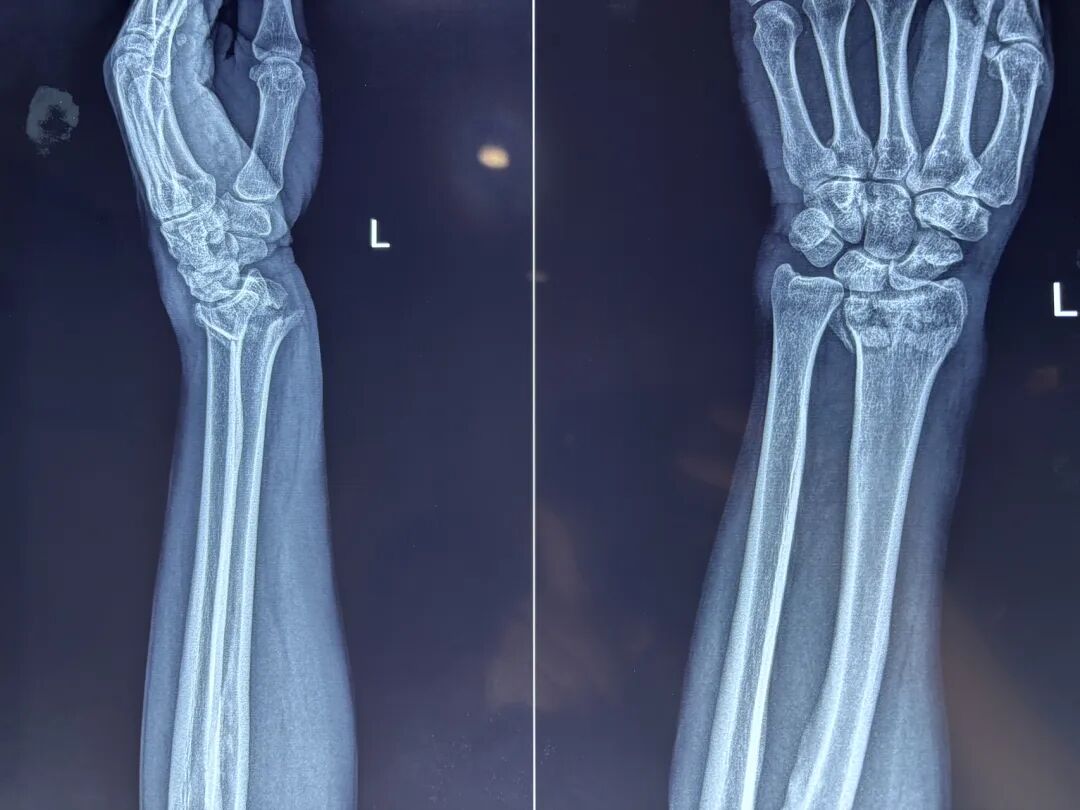

桡骨远端膨大,横断面略呈长方形,主要由松质骨组成,上端与桡骨干坚质骨相连,力学上是一个弱点,故此处易骨折。

桡骨茎突较尺骨茎突长约1~1.5cm,故桡骨远端关节面向尺侧倾斜15°~30°(平均 23°),还向掌倾斜 0°~23°(平均 11°)

桡骨远端关节面的倾斜角度 :

正常桡骨远端关节面向掌侧倾斜0°~23°平均11°

正常桡骨远端关节面向尺侧倾斜15°~30°,平均23°( 桡骨远端骨折后,其关节面的倾斜度改变)